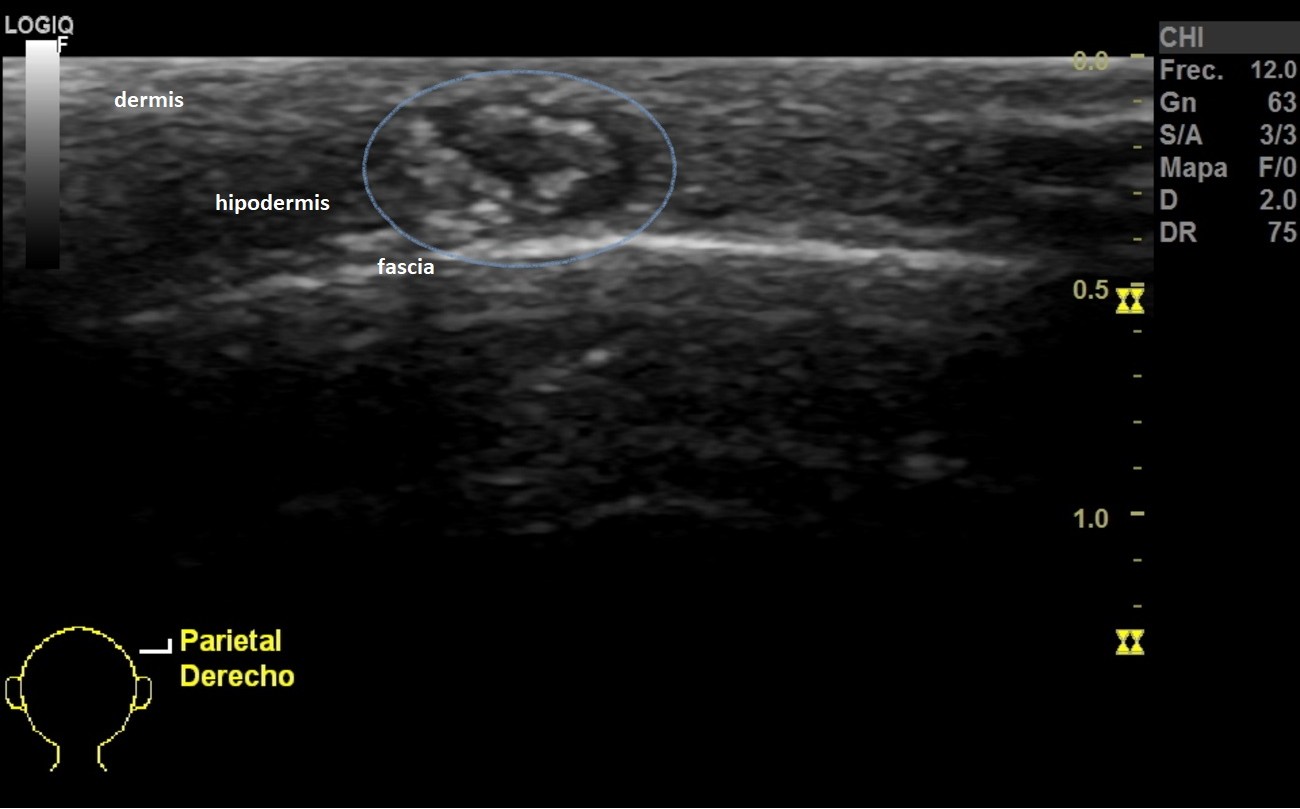

Niña de 8 años, sin antecedentes de interés, que consulta en Atención Primaria por un nódulo en el cuero cabelludo que han detectado recientemente. No asocia dolor ni fiebre ni clínica constitucional. A la exploración presenta un nódulo de consistencia dura de 1 x 1 cm de tamaño en la zona parietal derecha, sin cambios de coloración en su superficie ni signos de sobreinfección. Se realiza ecografía de la lesión objetivándose los hallazgos mostrados en la Figura 1.